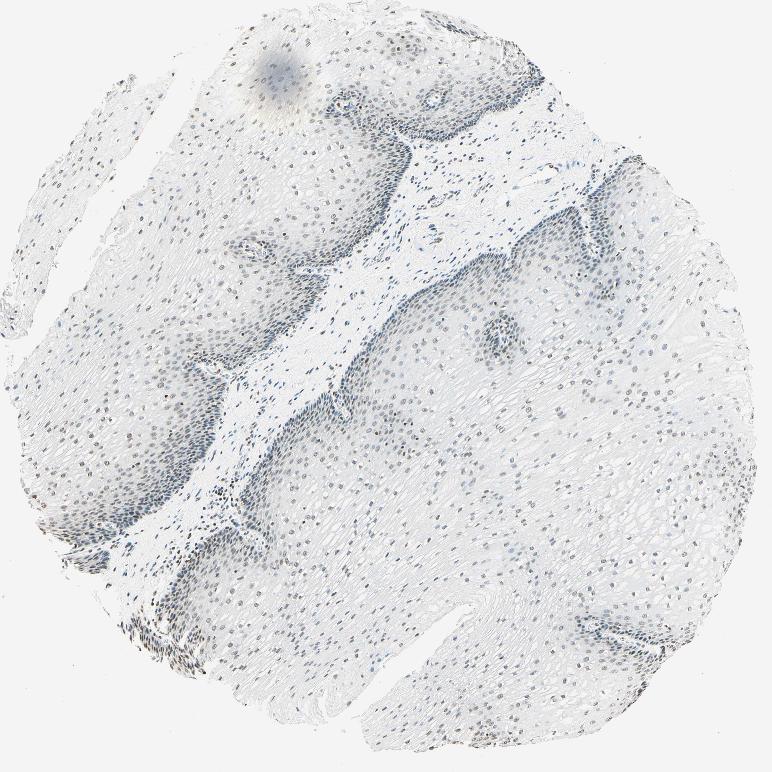

ESOPHAGUS - Antibody stainingi

Antibody staining in the annotated cell types in the current human tissue is reported as not detected, low, medium, or high, based on conventional immunohistochemistry profiling in selected tissues. This score is based on the combination of the staining intensity and fraction of stained cells.

Each image is clickable and will lead to virtual microscopy that enables deeper exploration of all samples and also displays staining intensity scores, fraction scores and subcellular localization as well as patient and tissue information for each sample.

Antibody CAB009572Antibody CAB070867Antibody CAB080131

Squamous epithelial cells Not detectedHighHigh